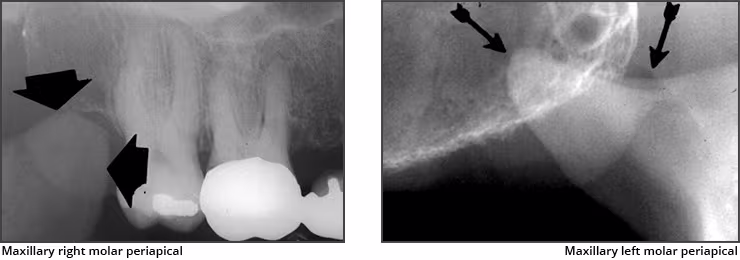

Maxillary sinus – The maxillary sinus is one of the paired paranasal sinuses. This prominent radiolucent air-filled cavity is located above the posterior teeth on the right and left sides of the maxilla. The sinus cavities are horizontally oblong bilateral structures with fine radiopaque borders. The maxillary sinus may contain septa which appear as radiopaque lines within the body of the sinus cavity. The size of the maxillary sinus can be quite variable and sometimes encroaches into the alveolar process, especially when posterior teeth are missing. Typically, the sinus appears uniform right to left. The maxillary sinus is sometimes referred to as the maxillary antrum and can be observed on both maxillary premolar and molar periapical images and partially on lateral-canine periapical images.

Coronoid process – The coronoid process of the mandible is the triangular bony portion of the anterosuperior aspect of the ramus. This mandibular structure can be recorded on maxillary molar periapical images as the ramus moves forward when the patient’s mouth is open. It appears as a bilateral triangular or thumb-like radiopacity on posterior maxillary images. The triangular portion projects forward toward the midline. The coronoid process is the only mandibular structure recorded on maxillary molar periapical images.